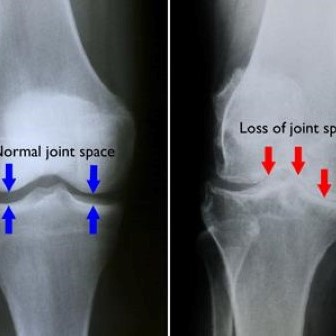

knee arthritis

Knee osteoarthritis is a degenerative joint condition caused by progressive loss of articular cartilage.